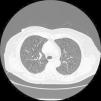

Observación clínicaMujer de 70 años, no fumadora, que consultó al Servicio de Medicina Interna por disnea de esfuerzo. Entre sus antecedentes patológicos destacaban un episodio de neumonía hacía 20 años y un tumor cerebral intervenido y tratado con radioterapia 3 años antes en otro hospital, del que desconocemos la histología, y del que le había quedado como secuela una parálisis facial izquierda. La exploración física fue normal, con saturación de oxígeno del 98%. Únicamente en la región periorbitaria destacaban unas discretas lesiones cutáneas indicativas de angiofibromas, sin detectarse lesiones en ninguna otra región corporal. En la radiografía de tórax (fig. 1) se observó un patrón intersticial, y la tomografía computarizada (fig. 2) evidenció múltiples imágenes quísticas en todo el campo pulmonar de ambos hemitórax, de morfología redonda y pared fina, sin estructuras vasculares en su interior ni engrosamiento de los septos. En la exploración funcional respiratoria la capacidad vital forzada (FVC) era de 1.970ml (un 68% del valor teórico), el volumen espiratorio forzado en el primer segundo (FEV1) de 1.260ml (un 61% del valor teórico) y FEV1/FVC de 63,65%. Se practicó una fibrobroncoscopia con lavado bronquioalveolar y biopsias transbronquiales. El estudio anatomopatológico (fig. 3) de las biopsias estableció el diagnóstico de linfangiomiomatosis pulmonar. Se llevó a cabo un estudio de receptores hormonales, que mostró positividad leve para los receptores de progesterona en numerosas células alrededor de las estructuras vasculares. A fin de descartar tumoraciones asociadas se efectuaron ecografía y tomografía computarizada abdominales, lo que permitió descubrir una lesión de densidad grasa en el polo inferior del riñón derecho, de 20mm, indicativa de angiomiolipoma, y 2 lesiones de características semejantes pero de menor tamaño en el polo inferior (7mm) y tercio medio (7,8mm) del riñón izquierdo.